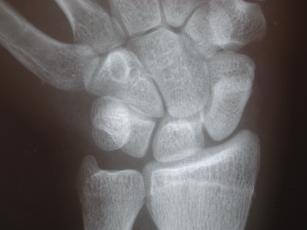

Die Diagnose eines Kahnbeinbruches ist schwierig und erfordert neben einer sorgfältigen klinischen Untersuchung u. U. mehrere Röntgenuntersuchungen. Wegen der gekippten Lage des Kahnbeins in der Handwurzel und seiner gekrümmten Form kommt das Kahnbein in den normalen Röntgenaufnahmen nur ungenügend zur Darstellung. Deshalb kann ein Kahnbeinbruch nicht immer durch Röntgen allein sicher festgestellt werden, v.a. wenn der Bruch unverschoben ist. Im Zweifelsfall kann die verletzte Hand nach 5-10 Tagen nochmals geröntgt werden. Oft lässt sich dann aufgrund der zwischenzeitlich eingetretenen Resorptionsvorgänge der Bruch erkennen.

Röntgenbilder in normaler Aufnahmetechnik

Spezielle Röntgenaufnahme zur besseren Darstellung des Kahnbeins

Die Diagnose wird anhand von Röntgenaufnahmen mit zusätzlichen Spezialaufnahmen des Kahnbeins gestellt. Eine Pseudarthrose ist deutlicher im Röntgenbild zu erkennen als ein frischer Bruch.

Normale Einstellung (links) und Spezialaufnahme (rechts)